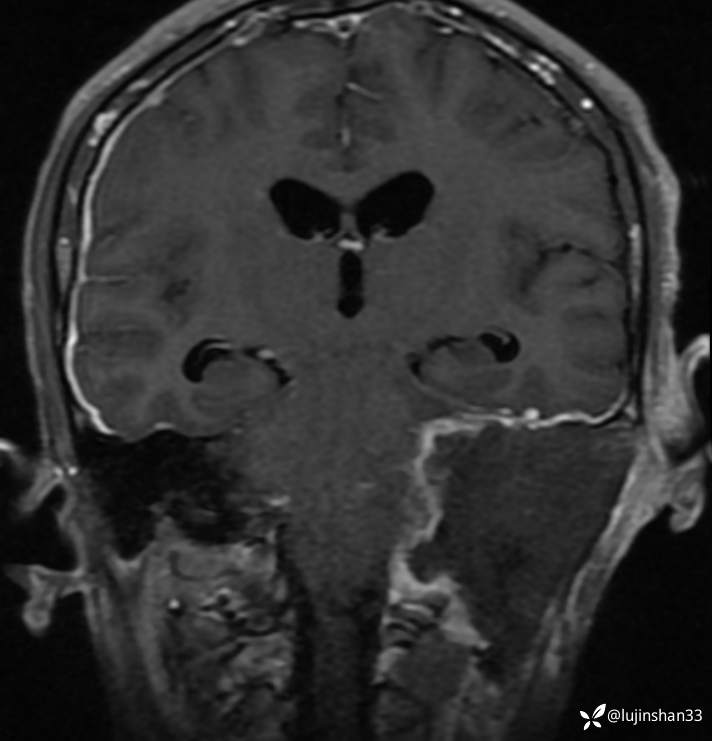

2019年2月首次手术后

首次手术有残留